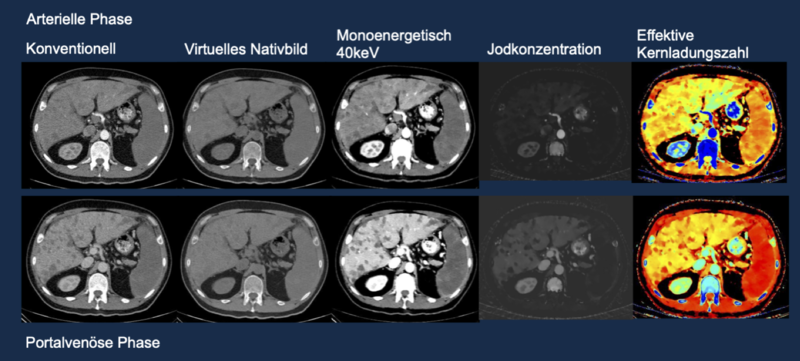

Mögliche Darstellungen bei der spektralen CT (Dual Energy). Oben ist die arterielle Kontrastmittelphase dargestellt, unten die spätere portalvenöse Phase. Beim virtuellen Nativbild wird das Kontrastmittel aus dem Bild herausgerechnet. Dadurch kann eine CT-Untersuchung ohne Kontrastmittel eingespart werden. Die monoenergetischen (40 keV) Bilder verstärken das Kontrastmittel, die Bilder der Jodkonzentration stellen das Kontrastmittel dar. Die Bilder der effektiven Kernladungszahl dienen der Gewebecharakterisierung. Alle Bilder einer Reihe können aus einer Untersuchung (eine Strahlenexposition) berechnet werden.